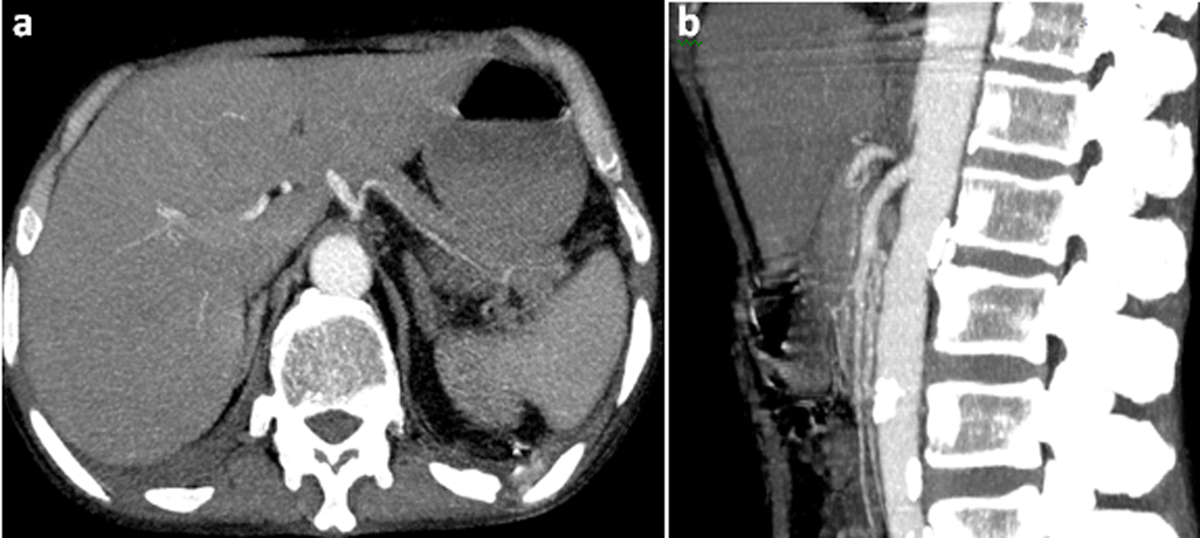

A contrast-enhanced abdominal computed tomography was performed. Axial images of portal phase demonstrated multiple wedge-shaped non-enhancing areas at the periphery of the spleen suggestive of splenic infarcts (Figure 1a). Splenic vein was permeable (Figure 1b). Axial and sagittal images of arterial phase revealed a small splenic artery related to severe stenosis and angulation of celiac axis caused by a thick soft tissue band (5 mm) anterior to the abdominal aorta creating a hooked appearance (Figure 2a, b). Coronal maximum intensity projection CT showed a prominent gastroduodenal artery with large collateral vessels around the pancreatic head (Figure 3). Median arcuate ligament syndrome causing splenic infarcts was retained and the patient was referred to vascular surgery service.

Figure 2